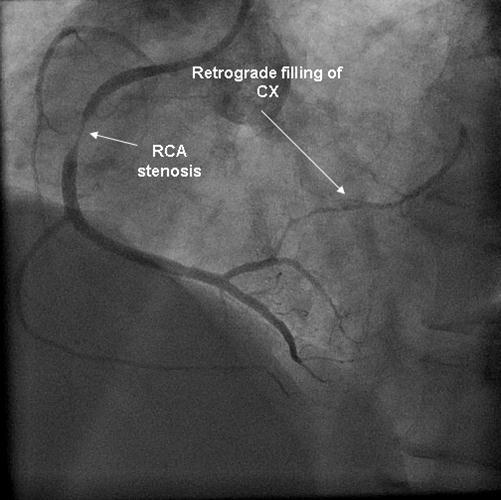

Coronary angiography was again performed. On injections into the left system, collaterals to the distal RCA were demonstrated (figure 1), arising from the left circumflex coronary artery (CX). Injections into the RCA demonstrated tight in-stent restenosis, (figure 2) and a drug eluting stent was successfully implanted. After the angioplasty, injections into the RCA were seen to retrogradely fill the CX (figure 3). The suspicion arose that maybe the left coronary artery had been inadvertently damaged during angiography, so the left coronary was again cannulated and injections performed, demonstrating entirely normal left main and CX arteries. However, the collateral flow that had previously been demonstrated from the CX to the RCA was no longer apparent. On review of the previous angiogram, it was noted that the RCA retrogradely filled the CX despite the original significant stenosis (figure 4). In essence, it became apparent that the bidirectional filling of the RCA from the CX and vice versa was in fact a direct continuity between the vessels and not collaterals, as free flow was noted from the RCA to the CX even when both arteries were completely patent.

Figure 4.Injection into the RCA in the first angiogram, with retrograde filling of CX.

Injection into the RCA in the first angiogram, with retrograde filling of CX.

There are a few interesting points about our patient's case. He demonstrated dynamic changes in the direction of coronary flow, in parallel to the development of a stenotic lesion. Firstly, in the original angiogram, there was flow from the RCA to the CX even though there was a significant stenosis. In his second angiogram, however, no such flow was demonstrated, maybe due to the longer and more critical restenosis that had developed in the stent. Secondly, at the start of both angiograms, there was flow from the CX to RCA, an appropriate finding as a collateral vessel in the presence of an obstructive lesion in the RCA. Thirdly, it seems that when both arteries are fully patent, the bidirectional flow changes to unidirectional, from the RCA to the CX.